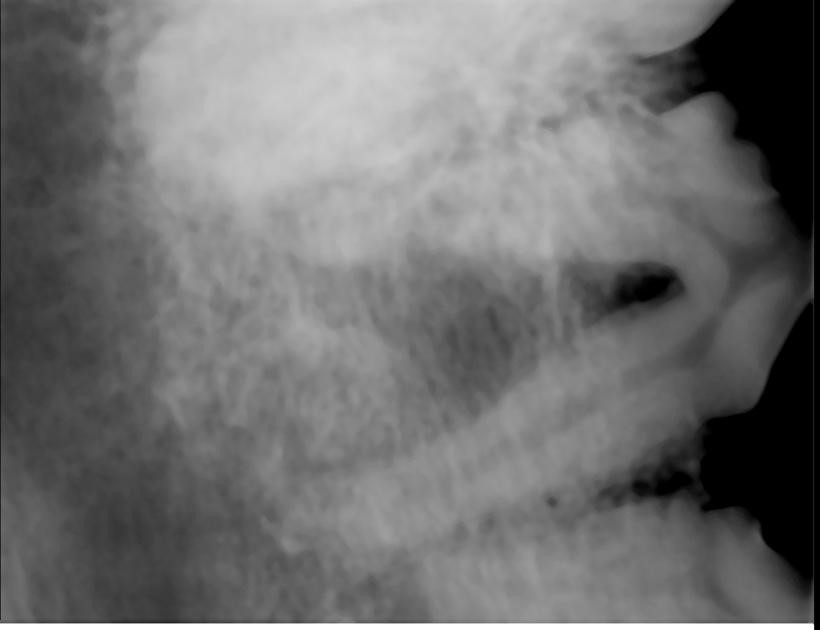

Mr. President, ein elfjähriger Briard, wurde von seiner Besitzerin in unserer Klinik vorgestellt. Der Hund frisst schlecht, und es befindet sich immer wieder Blut in seinem Wassernapf. Eine gründliche Untersuchung des Hundes zeigte eine Wucherung im Unterkiefer, die sich über mehrere Zähne erstreckte. Mr. President hatte zudem Zahnstein und Entzündungen am Zahnfleisch. Eine Röntgenaufnahme sollte nun Klarheit bringen. Um ein aussagekräftiges Röntgenbild erstellen zu können, ist eine Vollnarkose erforderlich. Während dieser Narkose sollte der Zahnstein entfernt und eine Gewebeprobe entnommen werden. Anhand dieser Gewebeprobe kann festgestellt werden, um welche Art von Wucherung es sich handelt. Anhand dieses Befundes wissen wir dann auch, ob es sich um eine gutartige oder eine bösartige Wucherung handelt und können entsprechend behandeln.

Die Gewebewucherung war dunkel pigmentiert und hatte eine blumenkohlartige Struktur. Mehrere Erkrankungen kamen zunächst in Frage. Als gutartige Wucherung kamen acanthomatöse Ameloblastome und sogenannte Epuliden (Zahnfleischwucherungen) in Frage. Die bösartige Variante sind Melanome, Fibrosarkome oder Plattenepithelkarzinome, um nur ein paar wenige zu nennen. Im Verlauf der weiteren Untersuchung unter Narkose zeigte sich, dass ein Zahn im Bereich der Wucherung lose ware. Der Knochen war ebenfalls betroffen. Der Zahn P4 im Oberkiefer biss in die Masse ein. Dies führte zu den Blutungen und war die Ursache für das Blut im Wassernapf von Mr. President. Beide Zähne, der lose Zahn und der, der in die Masse einbiss, wurden entfernt.

Die Heilungsaussichten sind sehr gut, wenn der Tumor vollständig mit dem Zahnhalteapparat entfernt wird. Es ist nicht erforderlich, extrem viel Gewebe um den Tumor herum zu entfernen. Die genauen Operationsgrenzen wurden vor der Operation durch eine Computertomographie bestimmt. Dieses Verfahren lässt die Knochenstruktur sehr gut erkennen. So lässt sich sehr viel genauer als mit einem Röntgenbild beurteilen, wie weit die Veränderung reicht. Der Tumor lässt sich anhand dieses Befundes komplett entfernen.